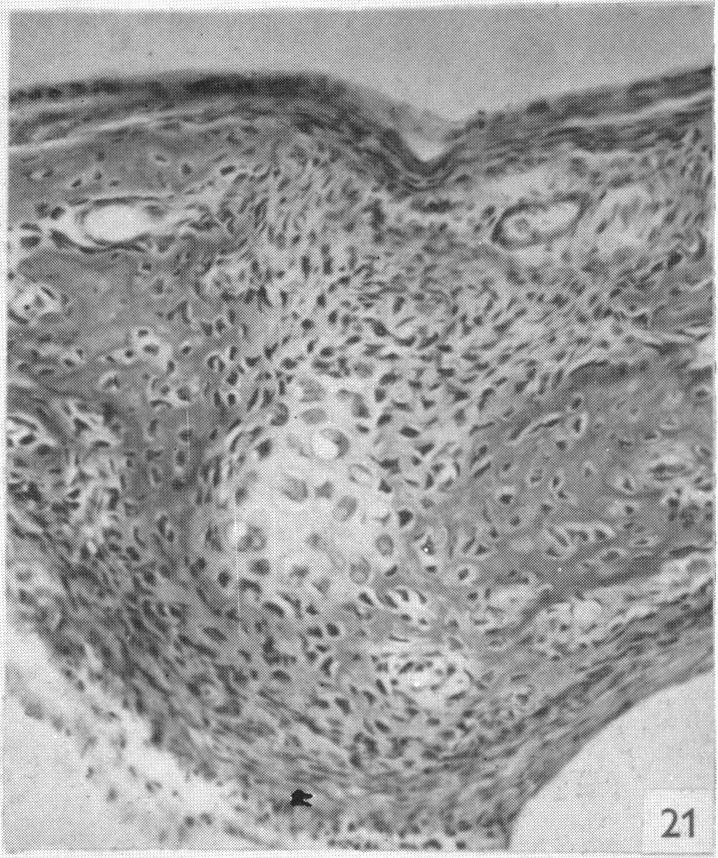

The structure and development of cranial and facial sutures.

PRITCHARD J J, SCOTT J H, GIRGIS F G

J Anat. 1956 Jan;90(1):73-86.